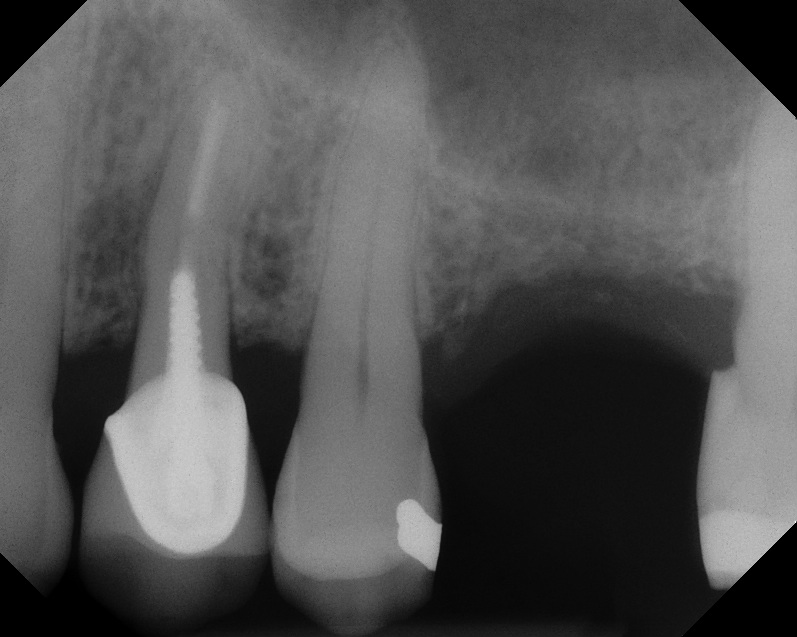

This patient was a 73-year-old man with only about 3.5 mm of native bone in the No. 3 site (Figure 20). The composite graft used here was a 50:50 mixture of DFDBA and deproteinized bovine bone mineral (Osteohealth, www.osteohealth.com) with approximately 40% calcium sulfate added. The implant was the same type and length as in Case 1 above. Figure 21 shows the area on the day of placement. In the CBCT scan on the day of placement (Figure 22), the native bone and bone graft were clearly discernable. However, the postoperative radiograph taken at 6.5 months (Figure 23) showed no marginal bone loss and a significantly denser appearance than when the graft was place. The membrane was raised about 7 mm to 8 mm. The final radiograph was taken after extraction of tooth No. 2 and after extraction of tooth No. 4 and immediate implant placement.

Case 3. Preoperative radiograph showing about 3.5 mm of ridge height.

Fig. 20

Day of sinus augmentation and implant placement in the No. 3 position. The sinus membrane has been raised about 7 mm to 8 mm.

Fig. 21

CBCT scan (Kodak 9000D) of No. 3 area, day of placement. Appearance of native bone and bone graft is clearly discernable.

Fig. 22

A 6.5-month postoperative radiograph. Teeth Nos. 2 and 4 have been extracted and an immediate implant had been placed in the No. 4 position.

Fig. 23